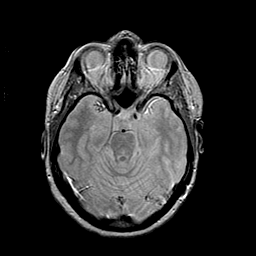

MR Study #2 -- Slice #20